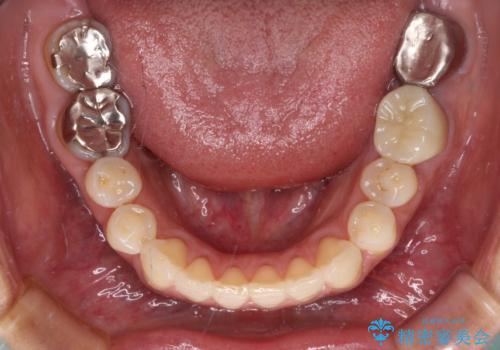

まずは左下奥歯の根管治療を行い、痛みが引いたことを確認してから矯正治療を開始しました。

後戻りは軽微であったため、インビザライン・ライトにて歯列を整えました。

矯正治療後には、左下奥歯の症状がないことを確認し、セラミッククラウンにて補綴治療を行うこととしました。

矯正治療後のレントゲン写真では、根尖部に認められた病変(骨の溶けていた像)は消失していることが分かりました。